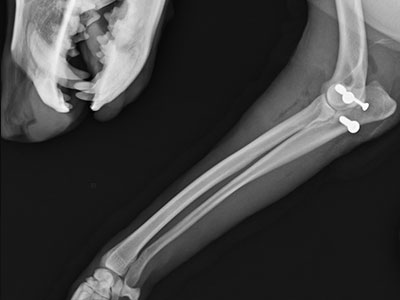

左前肢橈尺骨骨折

一個跳躍後左前肢突然不敢採地的壯壯,經X光確認為左前肢橈尺骨骨折,手術完美復位,目前已可正常行走。

術前

術後